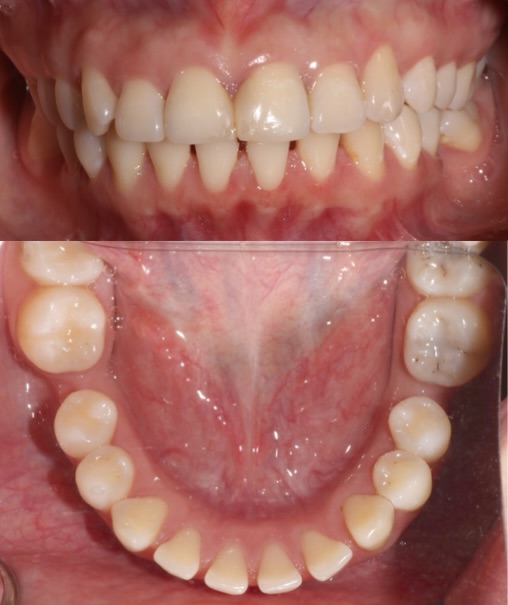

Full Mouth Rehabilitation

This full mouth rehabilitation involved a comprehensive approach: veneers were placed on vital anterior teeth for aesthetic enhancement, zirconia crowns on non-vital teeth for durability, and dental implants were used to replace missing posterior teeth on both lower sides. The treatment successfully restored function, esthetics, and long-term stability—planned and executed by the multidisciplinary team at Moral Dental Clinic.